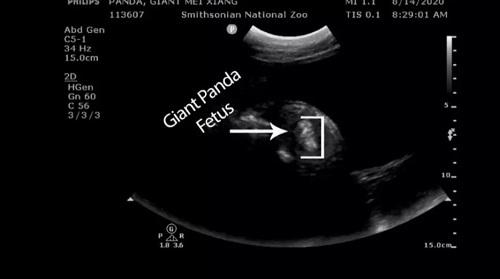

大熊猫美香的B超截图

中国小康网|法媒:旅美大熊猫美香被证实人工授精怀孕几天内产仔 B超显示熊猫宝宝踢腿游泳。动物园兽医用超音波检查22岁的美香时看见胚胎 。

园方指出 , 美香的宝宝“在羊水中踢脚、游泳 , 可以清楚看到胚胎的脊髓和血流”、“我们期待在这几天迎接健康的猫熊宝宝 。 ”

美香是于3月22日接受人工授精 , 接受园内公大猫熊“添添”的冷冻精子 。